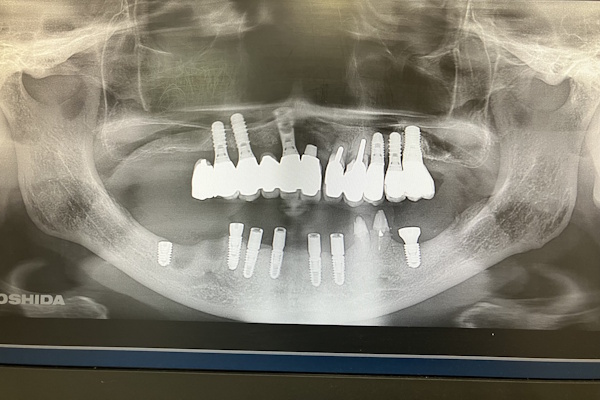

レントゲン画像